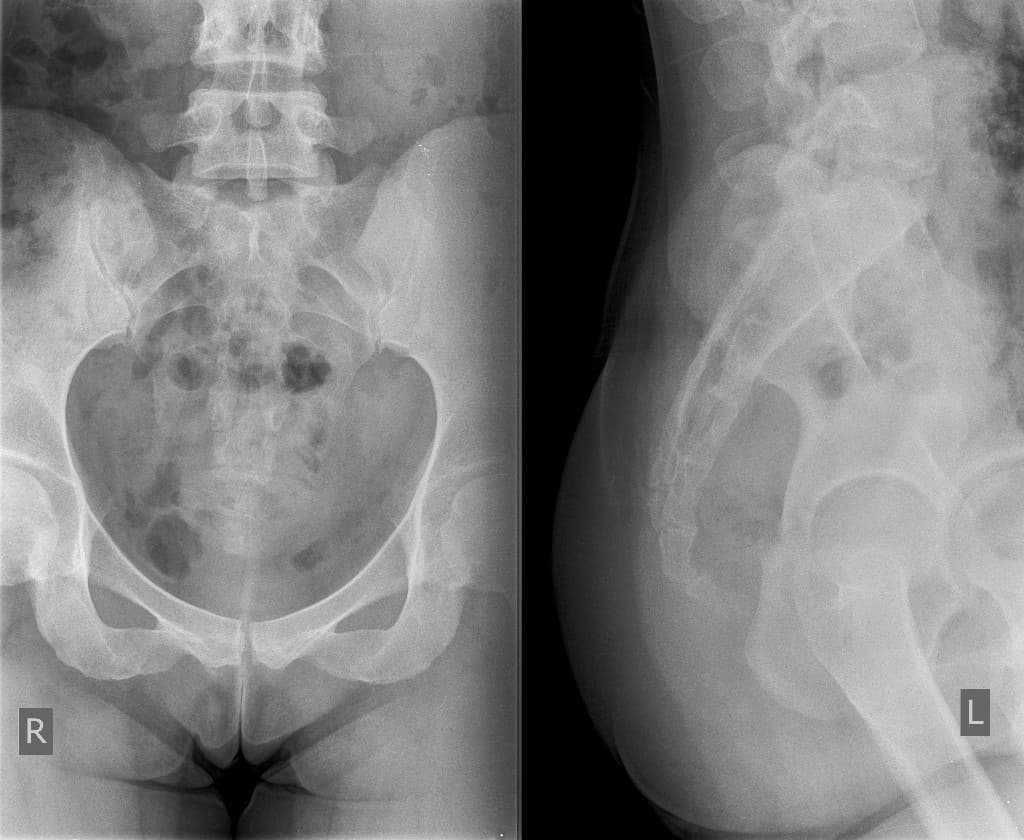

Рентгенография копчика назначается пациентам с подозрением на перелом или вывих копчика, трещину в костной ткани, гнойные или воспалительные процессы в этой области. Также врачи делают рентген-обследование при возможном наличии грыж и новообразований различного характера в копчике. Визуализация позвонков и остистых отростков на рентгенограмме позволяет диагностировать перелом копчика, его вывих, а также деформацию или вывих крестцово-копчикового соединения, в случае которого суставные поверхности перестают совпадать. Выявляется снижение высоты позвонков и возникновение остеофитов, определяется наличие остеомиелита, опухолей, метастазов, врожденных аномалий развития этого отдела.

Во время рентгенограммы в прямой проекции пациент ложится на спину, сгибает ноги в суставах коленей и таза для получения снимка крестца и выпрямляет их при обследовании копчика. Боковая проекция требует положения пациента лежа на боку с заведенными за голову руками и слегка согнутыми в коленях ногами.

Косые проекции в рентгенографии копчика используются для крестцово-копчикового соединения. Так как делают рентген копчика обычно в двух проекциях, вся процедура занимает не более 20 минут. После завершения обследования врач составляет заключение, исходя из полученных результатов, а терапевт или вертебролог ставит окончательный диагноз и назначает подходящее в каждом отдельном случае лечение.

Как проводят процедуру

Перед процедурой рентгена больной должен снять с себя все металлические предметы (украшения, часы), достать из карманов электронные приборы (телефон, айпад и т.д.). Рентген копчика делают в двух проекциях. Как делается рентген копчика, зависит от того, в какой проекции необходимо получить снимок. Больной ложится на специальную медицинскую кушетку и в зависимости от того, какая проекция необходима, рентгенолог указывает необходимые положения тела. Рентгеновский снимок копчика в прямой проекции делают, когда человек лежит на спине с выпрямленными ногами, для крестца – с согнутыми коленными и тазобедренными суставами.

Для боковой проекции снимка больной, лежа на боку, заводит обе верхние конечности за голову и немного сгибает колени. Для более детального исследования сочленения копчика и крестца делаются косые проекции.

Рентгеновские снимки копчика определяют:

- переломы со смещением и без;

- вывихи крестцово-копчикового сочленения;

- новообразования, злокачественные образования и метастазы;

- патологии костной ткани и др.